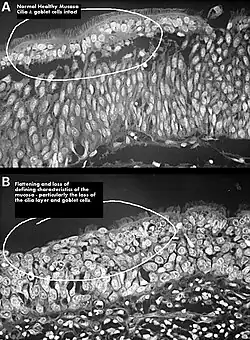

.jpg)

It has been proposed, that the airflow in ENS is changed so that most of the air flows through the middle meatus, compared to most of the air flowing through the inferior meatus in healthy individuals. This can be corrected via inferior meatus augmentation (IMAP surgery).[25]